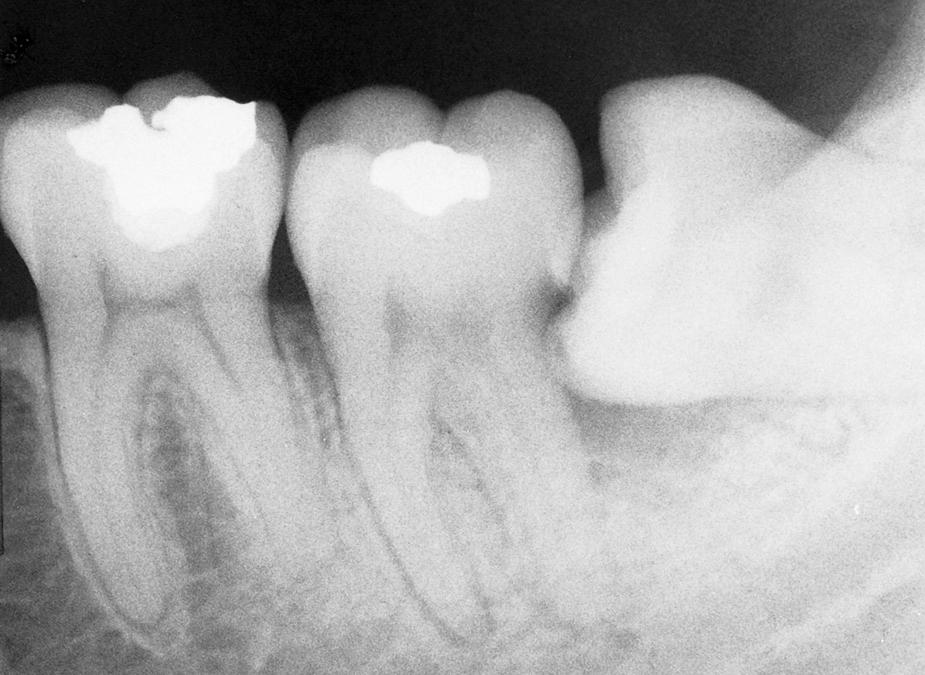

Erupted teeth adjacent to impacted teeth are predisposed to periodontal disease ( Figs. 10.1 and 10.2 ). The mere presence of an impacted mandibular third molar decreases the amount of bone on the distal aspect of an adjacent second molar. Because the most difficult tooth surface to keep clean is the distal aspect of the last tooth in the arch, patients commonly have gingival inflammation with apical migration of the gingival attachment on the distal aspect of the second molar. With even minor gingivitis, the causative bacteria gain access to a large portion of the root surface, which results in the early formation of periodontitis. Patients with impacted mandibular third molars often have deep periodontal pockets on the distal aspect of the second molars, even though they have normal sulcular depth in the remainder of the mouth.

Fig. 10.1, Radiograph of a mandibular third molar impacted against a second molar with bone loss resulting from the presence of a third molar.

Fig. 10.2, Radiographs showing variations of a mandibular third molar impacted against a second molar with severe bone loss resulting from periodontal disease and a third molar.